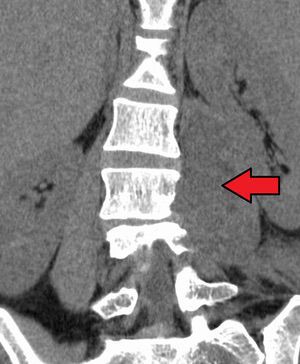

The psoas fascia covers the ant surface of the psoas muscle and can influence the direction taken by a tuberculous abscess.tuberculous disease of the thoracolumbar region of the vertebral column result in the destruction of the vertebral bodies with possible extension of pus laterally under the psoas fascia from there the pus tracks downward following the course of the psoas muscle and appears as a swelling in the upper part of the thigh below the inguinal ligament it may be mistaken for a femoral hernia